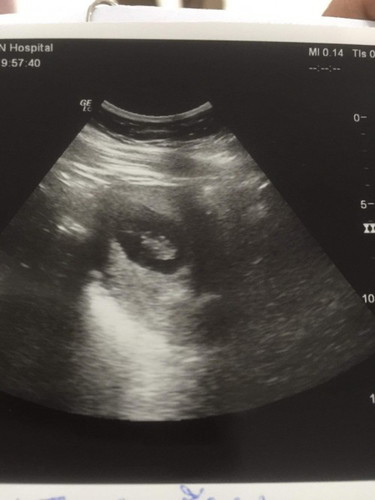

แม่ๆช่วยเดากันหน่อยคะ ว่าน้องกี่เดือนแล้ว คุณหมอให้ที่13W. แต่คุณหมอว่ายังไม่ชัว

ท้องแรกเมื่อ11ปีที่แล้ว ตอน14วีคค่ะ ชัดแจ๋วแว๋วเลย ส่วนท้องปัจจุบันนี้เราซาวด์เห็นเป็นตัวเด็กชัดๆเลยก็ตอน9-10วีคค่ะ ของแม่น่าจะยังอ่อนๆอยู่ไหมคะ ปกติจะมีอายุครรภ์แจ้งในใบซาวด์นะคะวัดจากขนาดตัวน้อง

หาก 13 W จะเห็นเป็นตัวน้องชัดแล้วนะคะ ถ้าแม่กังวลลองเปลี่ยนที่ซาวดูค่ะ

รูปนี้ตอน11wคะ ถ้าคุณแม่ไม่สบายใจคุณแม่ลองซาวด์ใหม่นะคะ